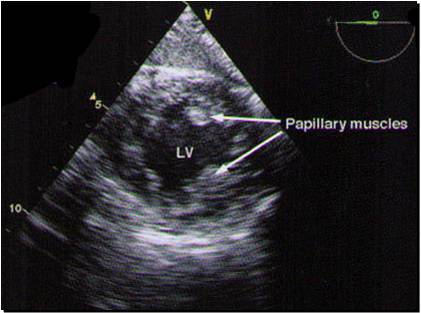

A 2 chamber view